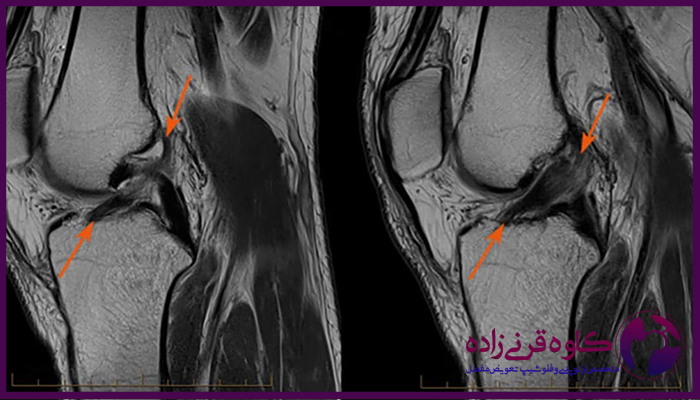

برای تایید تشخیص و بررسی شدت آسیب، معمولا از تصویربرداری به ویژه ام آر آی استفاده میشود که پارگی رباط ها و سایر آسیب ها را به طور دقیق نشان میدهد. در برخی موارد، آرتروسکوپی زانو نیز برای بررسی وضعیت داخلی زانو و تعیین روش درمانی مناسب مورد نیاز است.

عکس ام ار ای پارگی رباط زانو